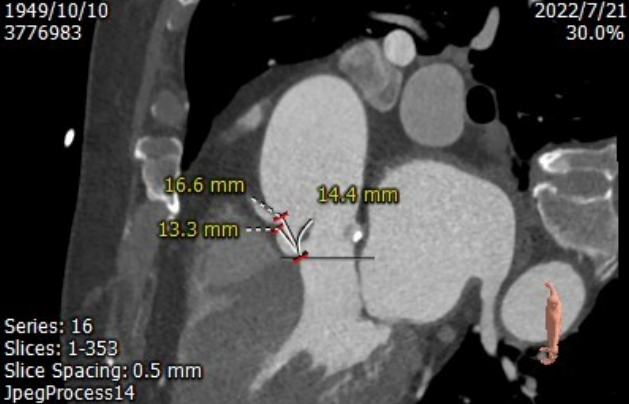

CT测量

主动脉根部CT测量

左室流出道周长:71.5mm

瓣环周长:72.1mm

升主动脉扩张,周长:139.7mm

右冠高度:13.3mm;瓣叶长度:14.4mm

左冠高度:13.4mm;瓣叶长度:12.6mm